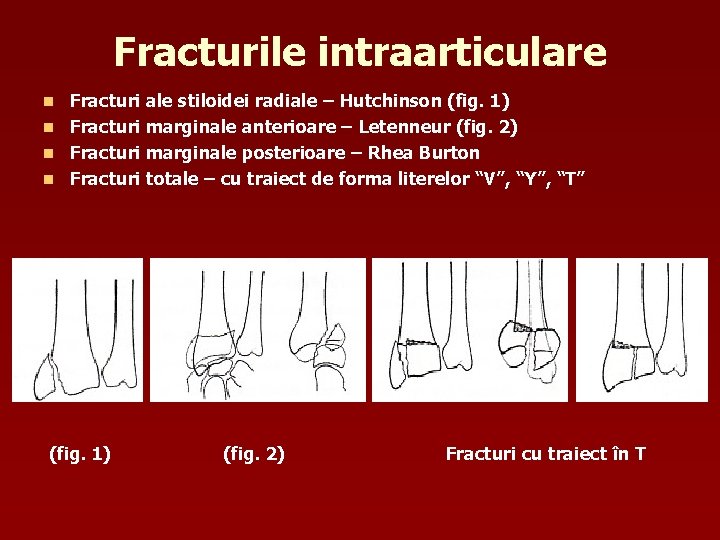

Fracturile intraarticulare Fracturi ale stiloidei radiale – Hutchinson (fig. 1) n Fracturi marginale anterioare – Letenneur (fig. 2) n Fracturi marginale posterioare – Rhea Burton n Fracturi totale – cu traiect de forma literelor “V”, “Y”, “T” n (fig. 1) (fig. 2) Fracturi cu traiect în T